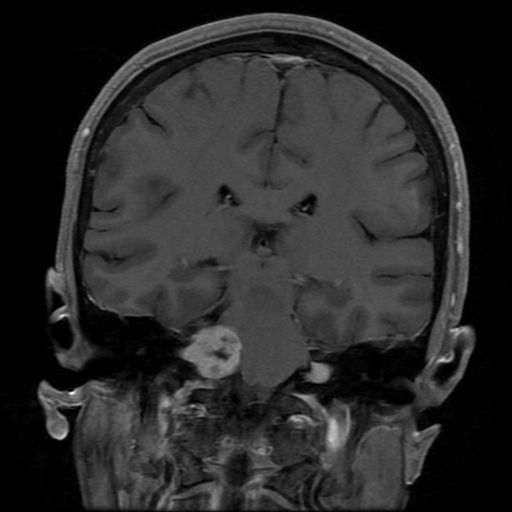

Acoustic Neuroma (AN): Acoustic neuromas are non-cancerous tumors that develop along the vestibulocochlear, or 8th, cranial nerve. ANs are also sometimes referred to as acoustic schwannomas as they arise from the Schwann cells which form the covering of the nerves. Approximately 3,000 new cases are diagnosed each year in the United States. They are most commonly found in adults in their 50s and 60s and males and females are affected equally as often.

Usually, these tumors begin to grow within the internal auditory canal. In some cases, as they get bigger, they can enter the cerebellopontine angle between the brain stem and pons. Large tumors can cause blockage of the spinal fluid flow through the brain and can result in increased intracranial pressure. In addition, ANs, because of their location, can cause pressure on other cranial nerves resulting in deficits. Symptoms may include decreased hearing, imbalance, impaired gait, dizziness or vertigo associated with nausea and vomiting, a sensation of pressure in the ear, and often tinnitus, a high pitched ringing or hissing sound. Large tumors that affect additional cranial nerves may cause facial weakness, decreased facial sensation, and loss of taste on the same side as the tumor. The tumors that grow large enough o cause increased intracranial pressure may present with headache, vomiting, and changes in consciousness.